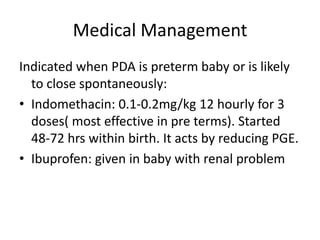

Text Patent Ductus Arteriosus PDA in Premature Infants

PATENT DUCTUS ARTERIOSUS PDA IN CHILDREN Dr Gaurav Agrawal

PDA in Preterm Infants Neonatal Network South East

25 PDA in preterm infants 75 PATENT DUCTUS ARTERIOSUS IN PRETERM